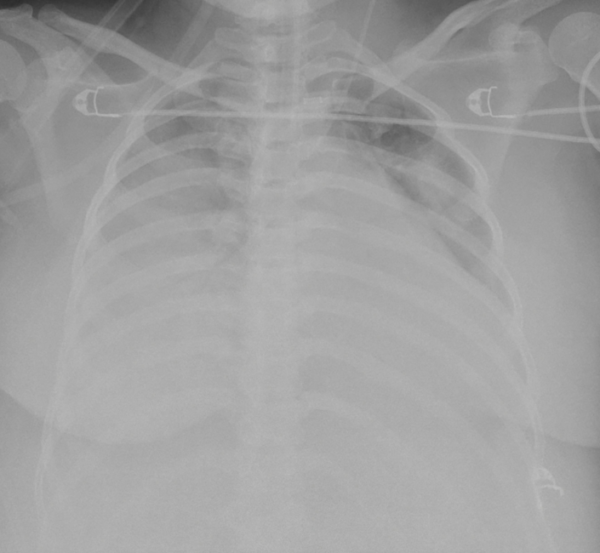

Hình ảnh tổn thương phổi nặng tại thời điểm can thiệp VV-ECMO |

Nhận định về ca bệnh, ThS.BS Giang Minh Nhật – Trưởng đơn vị Hồi sức tích cực tim mạch – Bệnh viện Nhân dân Gia Định cho biết : “Khi được chuyển đến bệnh viện Nhân dân Gia Định, tình trạng suy hô hấp của bệnh nhân diễn tiến nguy hiểm đến tính mạng (hội chứng nguy kịch hô hấp cấp) không đáp ứng thở máy xâm lấn, tổn thương phổi trên Xquang ngực chiếm hơn 80% thể tích phổi.

Hình ảnh tổn thương phổi nặng tại thời điểm can thiệp VV-ECMO